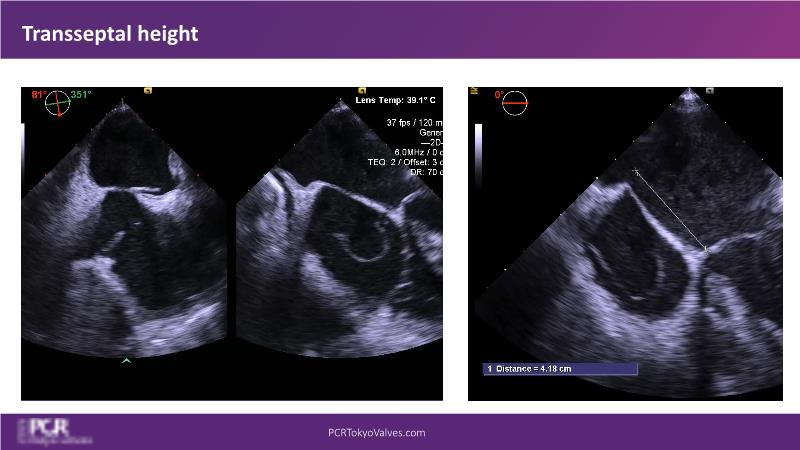

Watch this session to get an overview of a new TEER device, follow the step-by-step procedure related to initial experiences with this device for a Japanese patient with degenerative mitral regurgitation, learn about the latest data from RCT and registries, and follow discussions of challenging TEER cases!

- To learn procedural step-by-step of novel device